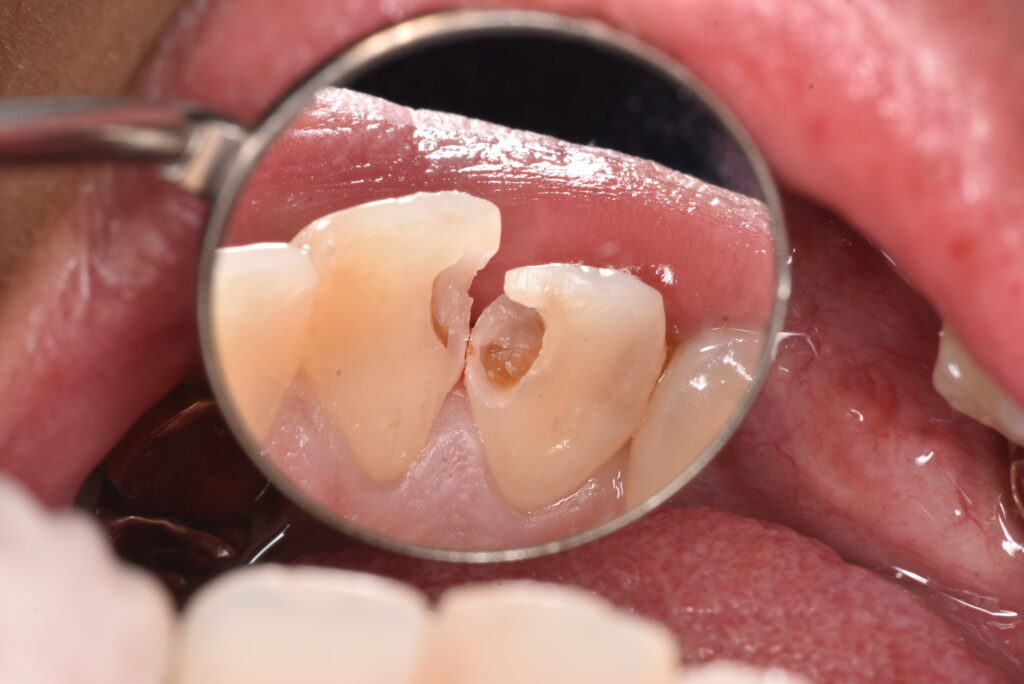

白のつめもののなかの一例

実際の処置例をお見せしていきます。。

処置する前から、怪しい状態なのはなんとなくわかると思います。では、この方は症状はあったのか?

→Noです。ありませんでした。つめものの周りに隙間があったのか?それもNoです。

削った写真を見ていただくと、中で汚染されている部分がわかると思います。一番最後の写真の中央にあるのは、むし歯の部分ではなく、神経の入り口です。神経は基本的に歯の奥の方に隠れています。むし歯を取り除くとそれが見える・・・それは正常なことなのでしょうか?